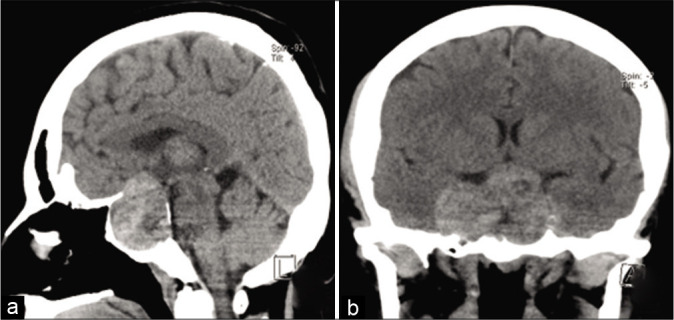

一名49歲的女性被轉(zhuǎn)介到醫(yī)院作為一個(gè)大型無(wú)癥狀垂體大腺瘤的病例進(jìn)行外科治療。在多方位的臨床評(píng)估中,患者報(bào)告稱,在過(guò)去的2年中,她一直抱怨慢性雙顳頭痛、原因不明的易疲勞性和緩慢的進(jìn)行性視力下降。她還報(bào)告說(shuō)患有高血壓,通過(guò)藥物治療可以得到充分控制。她報(bào)告沒有任何外科手術(shù)史或任何家族性疾病。檢查時(shí),除了視力問題外,顱神經(jīng)評(píng)估并不。詳細(xì)的眼科檢查顯示雙眼視力下降,更多在左側(cè),伴有雙顳同向偏盲。內(nèi)分泌評(píng)估和生化檢查顯示中樞性甲狀腺功能減退,可通過(guò)左旋甲狀腺素替代療法進(jìn)行治療。大腦的計(jì)算機(jī)地形圖成像顯示一個(gè)稍高密度的大型鞍/鞍上腫塊,向兩側(cè)海綿竇延伸,右側(cè)鞍旁延伸。病變擴(kuò)大了骨蝶鞍,伴有上斜坡的凹陷和重塑【圖1】。